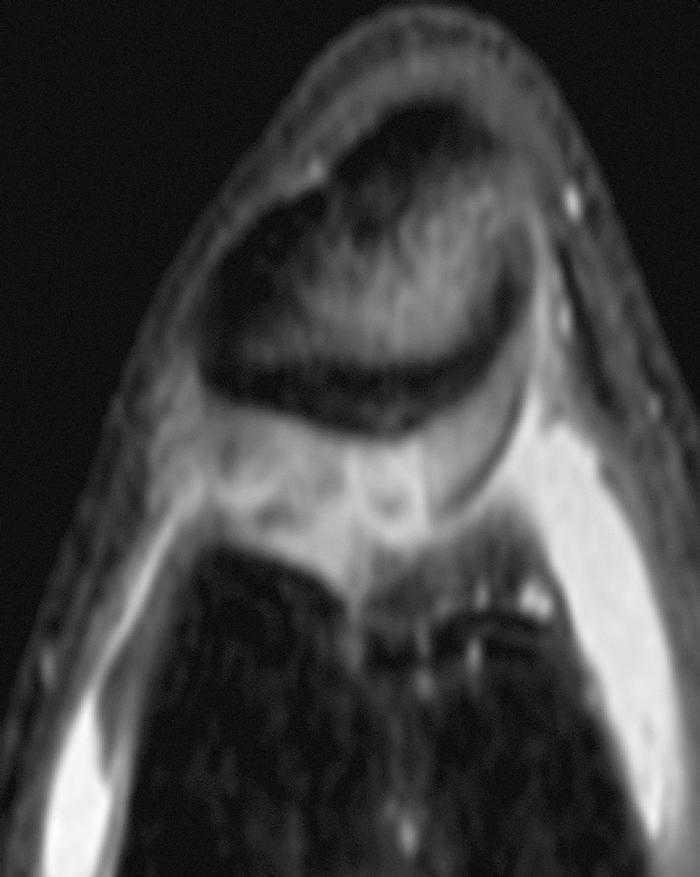

Figura 3 RM. Imatge potenciada en T2 amb supressió de greix. Lesió condral àmplia en ròtula, faceta externa i cresta condral.

• Lesió condral àmplia en faceta externa i cresta de ròtula, de gruix parcial.